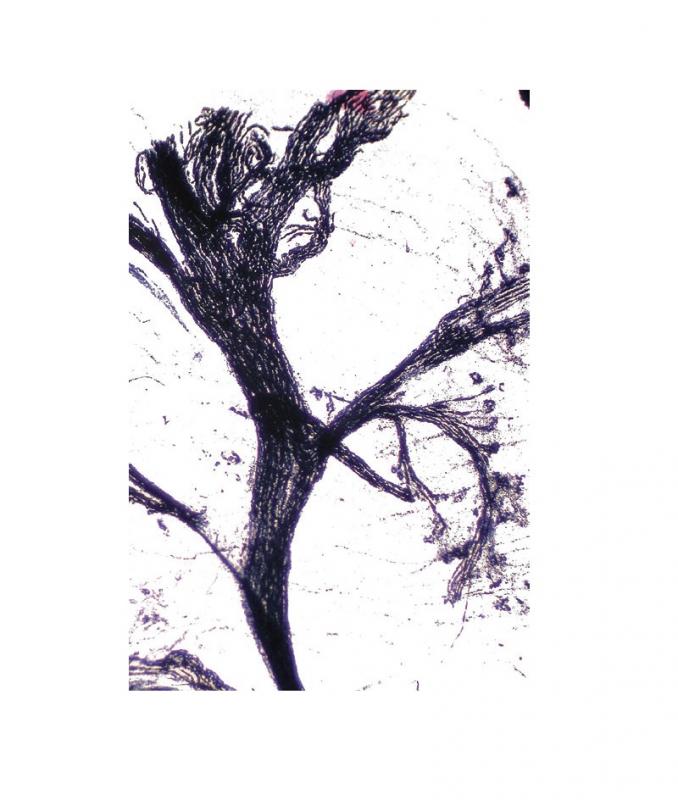

Préparation microscopique: Cerveau de rat (Cajal) CT

Cervelet, rat Coupe transversale (CT) Coloration Cajal Préparation microscopique - Biologie animale - Histologie des verterbrés - Système nerveux À l'unité